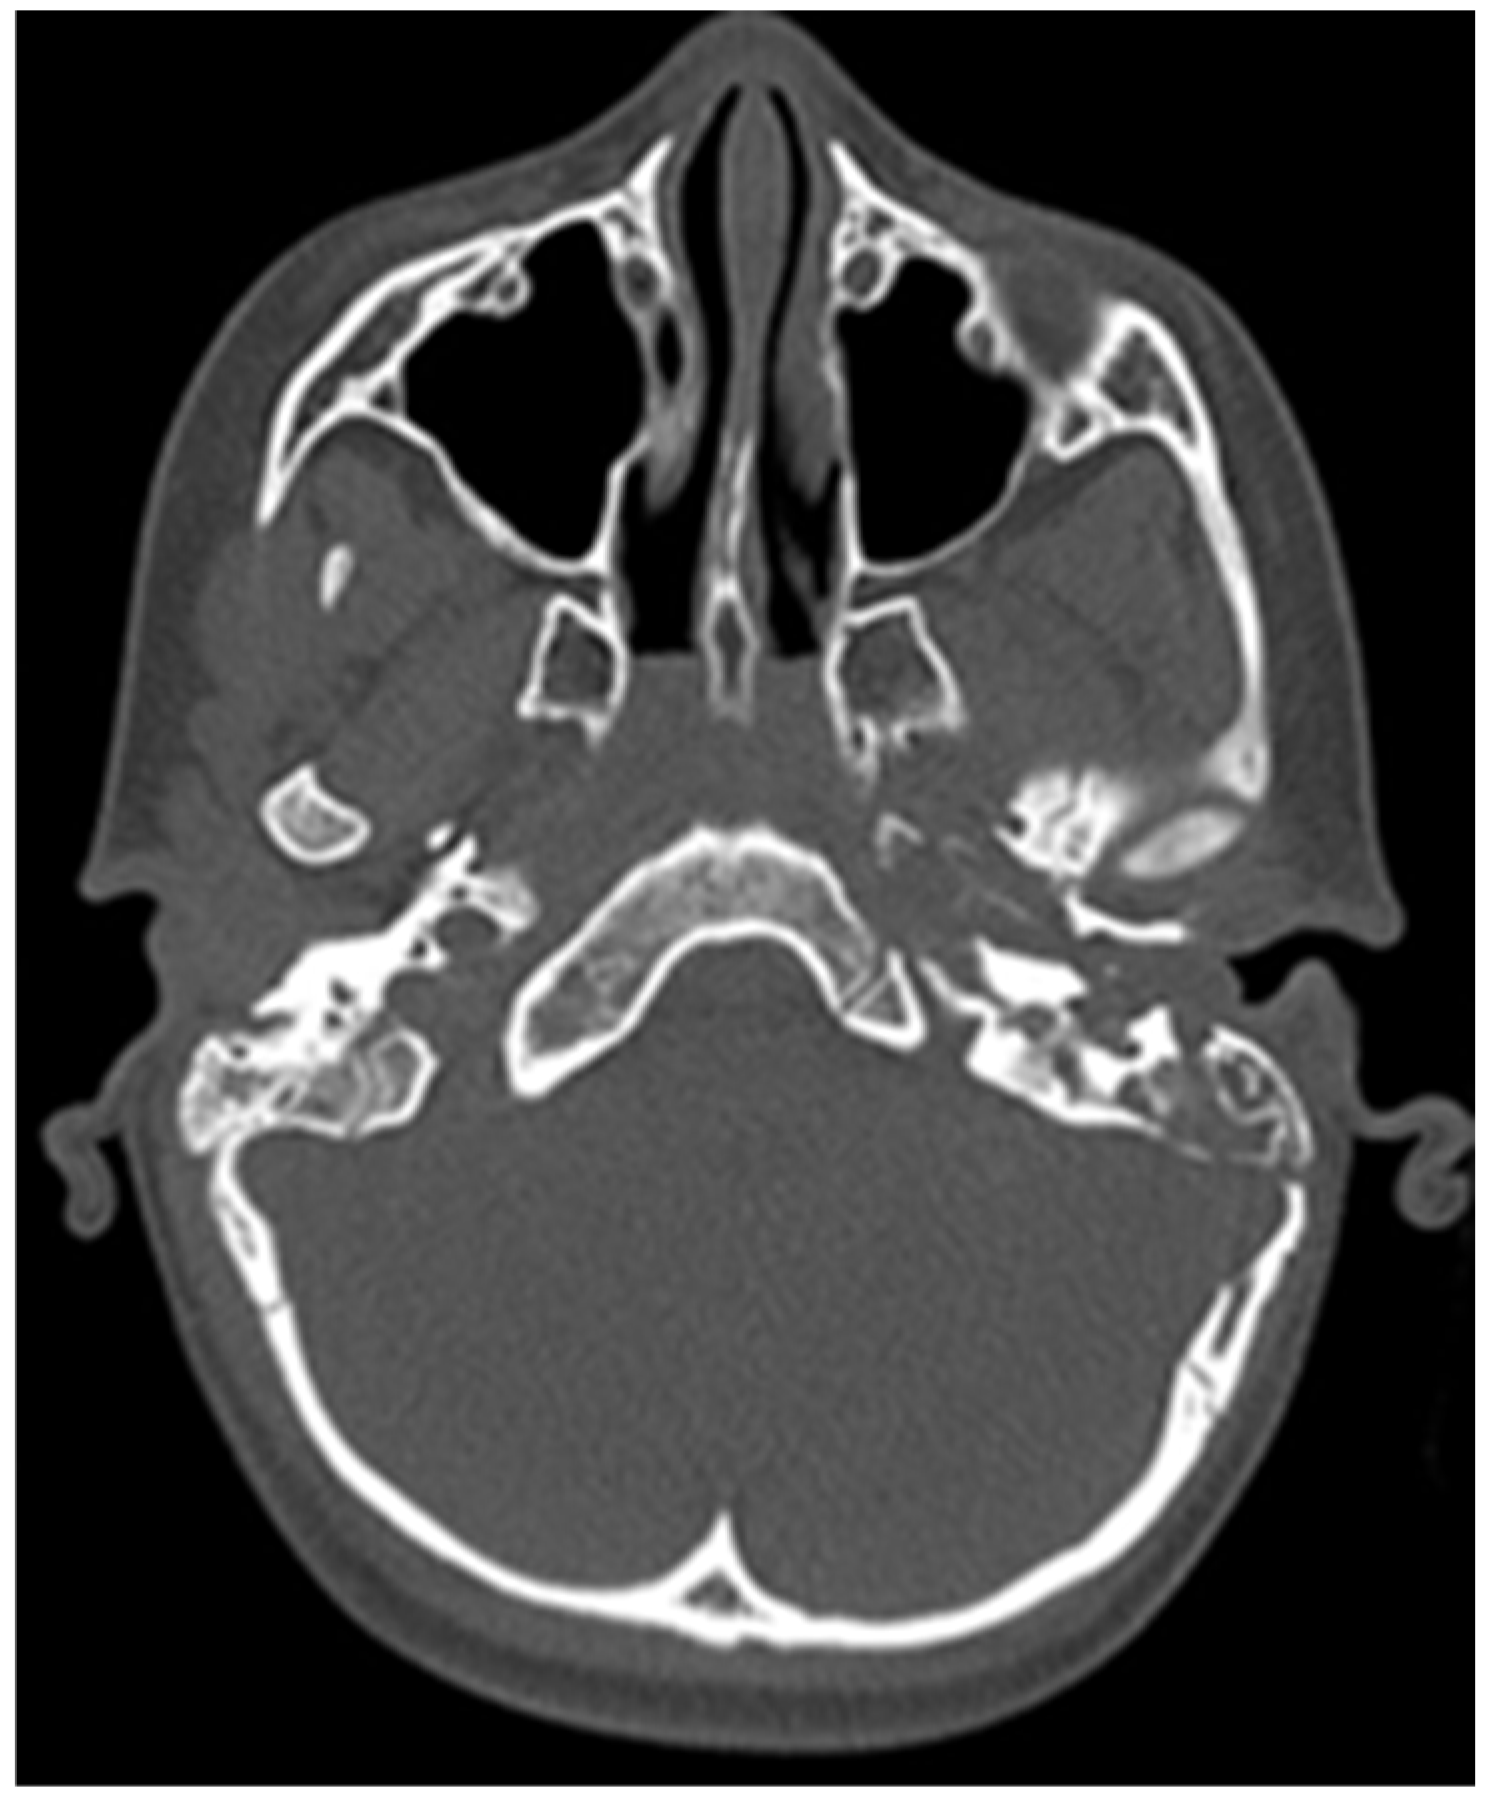

CT of the head was performed, which showed destruction of the left mastoid process from a soft tissue tumour mass, which involves the cavities of the middle ear, tympanic cavity and the external auditory channel (Figure 2 and Figure 3).

Figure 2. Initial CT of the patient.

Figure 3. Initial CT of the patient.